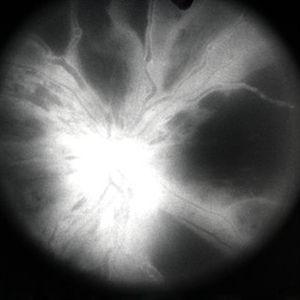

CRVO ischemic - FA 1

Jan 11 2013 by Alex P. Hunyor, MD

Severely ischaemic central retinal vein obstruction (CRVO), right eye - early fluorescein angiogram showing almost complete capillary non-perfusion.

Condition/keywords: ischemic CRVO